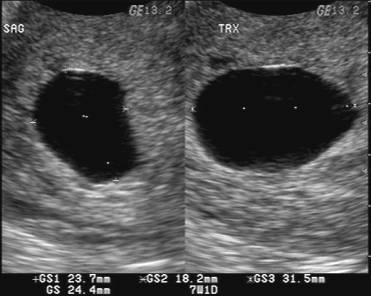

Kapan Kehamilan Kembar Terdeteksi

Kapan Kehamilan Kembar Terdeteksi

Pengalaman Hamil Kembar - The Urban Mama

Pengalaman Hamil Kembar - The Urban Mama

Ternyata Positif Sedang Hamil Kembar-Keluarga si Kembar

Ternyata Positif Sedang Hamil Kembar-Keluarga si Kembar